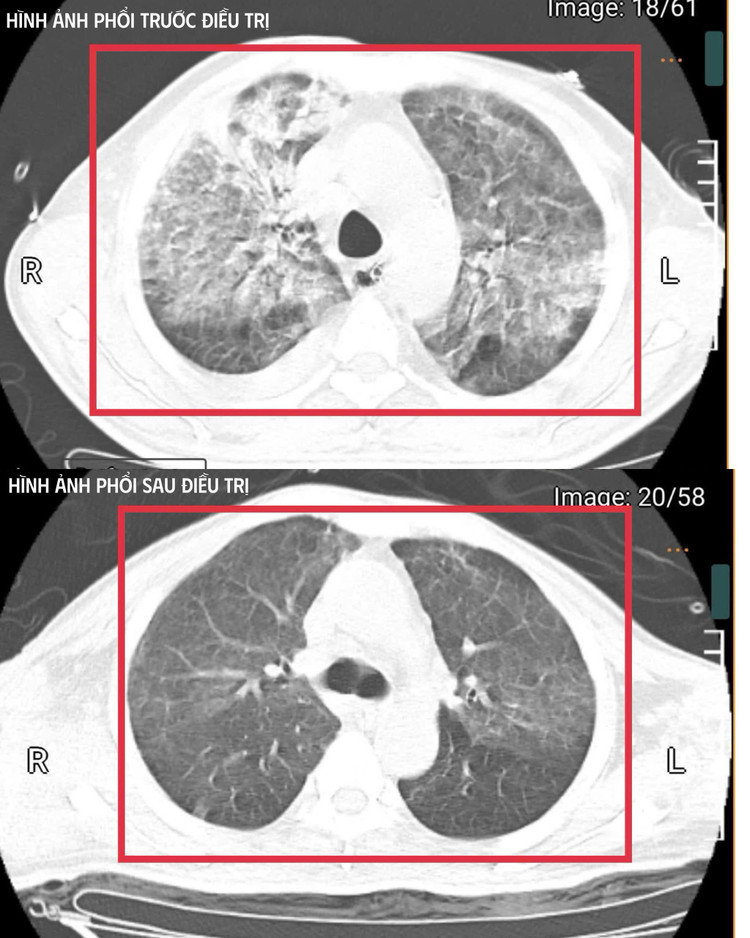

Hình ảnh tổn thương phổi của bệnh nhân trước và sau điều trị - Ảnh BVCC